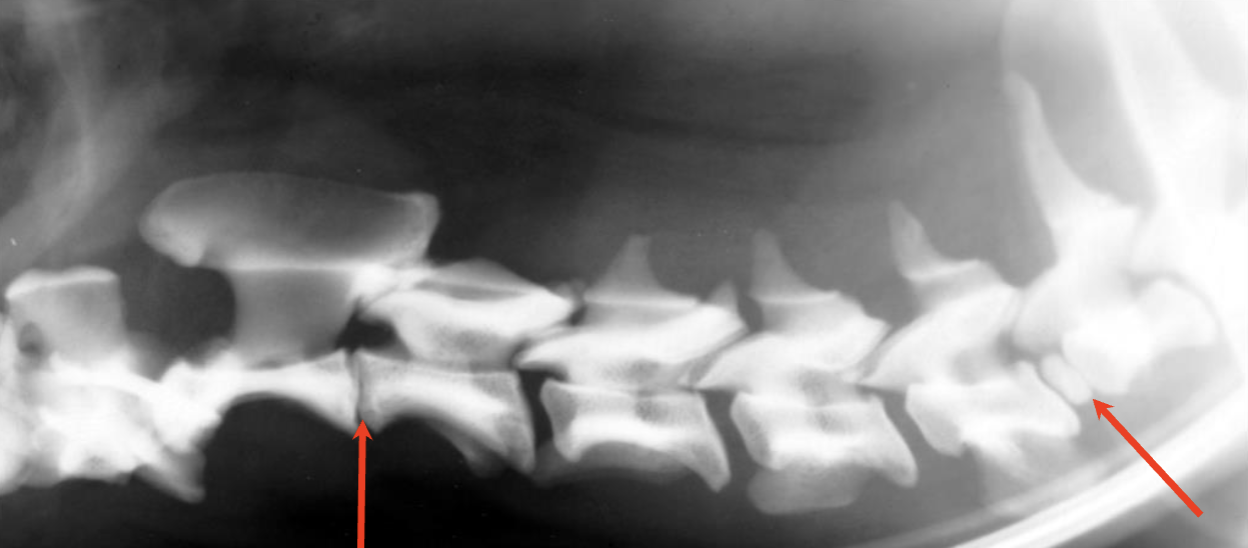

What are the abnormalities shown in this radiograph?

A

left arrow: narrowed disc space between C2 and C3

right arrow: calcified disc between C6 and C7